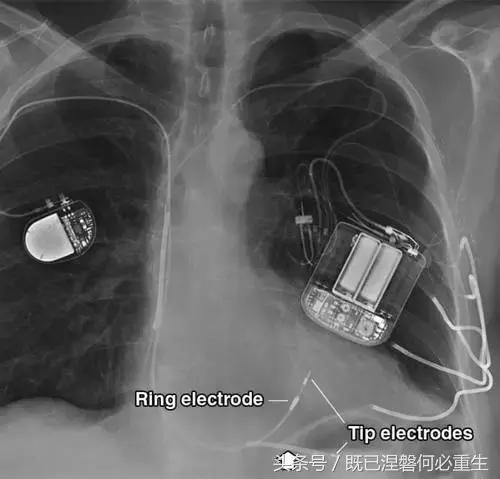

图。 3A 普通电极和电极导管固定在一个62岁的男人。A,额部胸片显示右侧的Medtronic单室起搏器和左侧的CPI(心脏起搏器公司)植入式心律转复除颤器(ICD)。 每个装置具有不同类型的双极右心室(RV)导联。 尖端电极位于两个RV引线的终端,而起搏器引线上的短的近端金属不透明是环形电极。 集成双极ICD引线使用RV冲击线圈作为其环电极(箭头)。 仅具有顶端电极和没有冲击线圈的引线是单极的,并且使用发生器的金属外壳作为等效的环形电极(未示出)。 左胸壁的曲线金属混浊是皮下阵列,其用于在需要大量能量去纤颤的患者中降低(改善)除颤阈值。 皮下阵列将更多的心室壁纳入冲击范围,比单独的休克线圈作用范围更广。

图。 3A 普通电极和电极导管固定在一个62岁的男人。B,电极的放大图像。 起搏器导线被主动固定并通过心肌中的螺钉尖保持在适当位置。 ICD导线被动地固定有射线可透射的尖齿。 胫骨陷入小梁骨内膜(或心房),并且导线变得锚定有纤维化的发展,这通常需要6周至3个月。